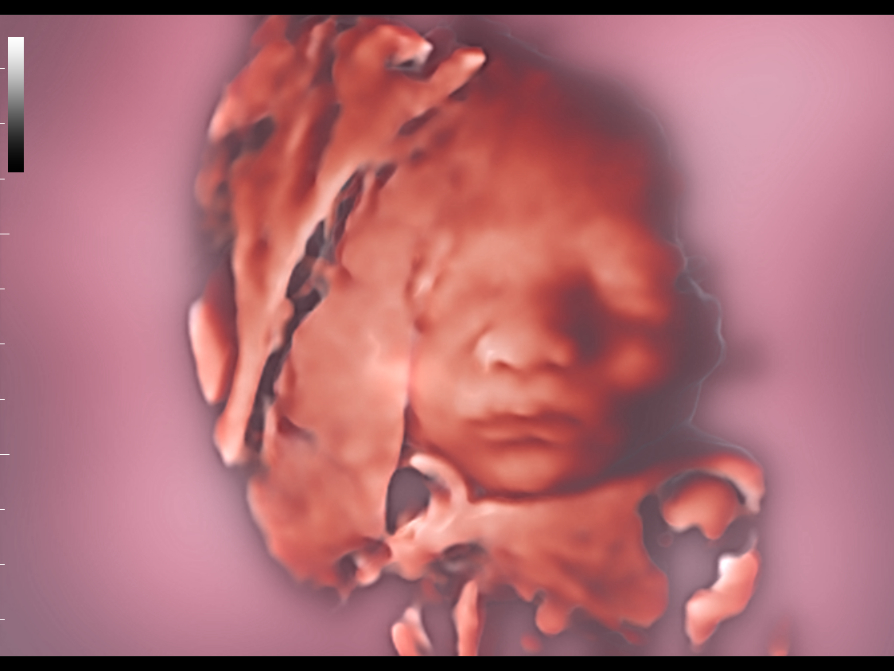

The volume imaging of fetal face is very important for the obstetric doctors whehere they make the face malformation diagnosis or a fully communication with parents. We deeply understand how Nuewa users need more intuitive fetal stereoscopic imaging to help parents quickly establish parent-child links at different gestational weeks.